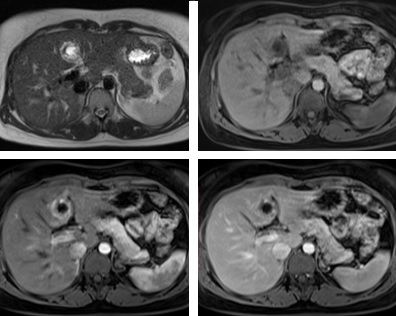

Hình 3, 4, 5, 6: theo thứ tự Axial HASTE, T1 FS, T1FS CM thì động mạch và thì tĩnh mạch: cho thấy có khối choán chỗ ở hạ phân thùy IV, cấu trúc: phần ngoại biên tín hiệu mô dày# 6-7mm, bao cấu trúc tín hiệu dịch d# 11mm, phần ngoại biên có tín hiệu thấp trên T1W, cao nhẹ trên T2W, bắt thuốc mạnh ở thì động mạch và vẫn còn tín hiệu cao nhẹ trên thì tĩnh mạch.

Hình 7: Tổn thương nằm sát nhánh trái tĩnh mạch cửa.

MRI: Gan ở hạ phân thùy IVb có tổn thương 26 x 27 mm, với viền mô đặc dày 6-7 mm ở ngoại vi bao quanh cấu trúc dạng dịch 11 mm. Phần mô đặc có tín hiệu thấp trên T1W, cao nhẹ trên T2W, bắt thuốc tương phản mạnh không đồng nhất. Tổn thương có vị trí nằm rất sát nhánh trái tĩnh mạch cửa. Tĩnh mạch cửa và các tĩnh mạch gan bình thường.

Chẩn đoán MRI: Tổn thương ở hạ phân thùy IVb gan trái, gợi ý thai ngoài tử cung.

MRI: Hình ảnh tổn thương hình tròn với viền dày tăng tín hiệu trên T2W và giảm tín hiệu trên T1. Chụp với thuốc cản từ cho hình ảnh bắt thuốc mạnh dạng vòng không liên tục ở thì động mạch và vẫn còn bắt thuốc ở thì tĩnh mạch với trung tâm không bắt thuốc.